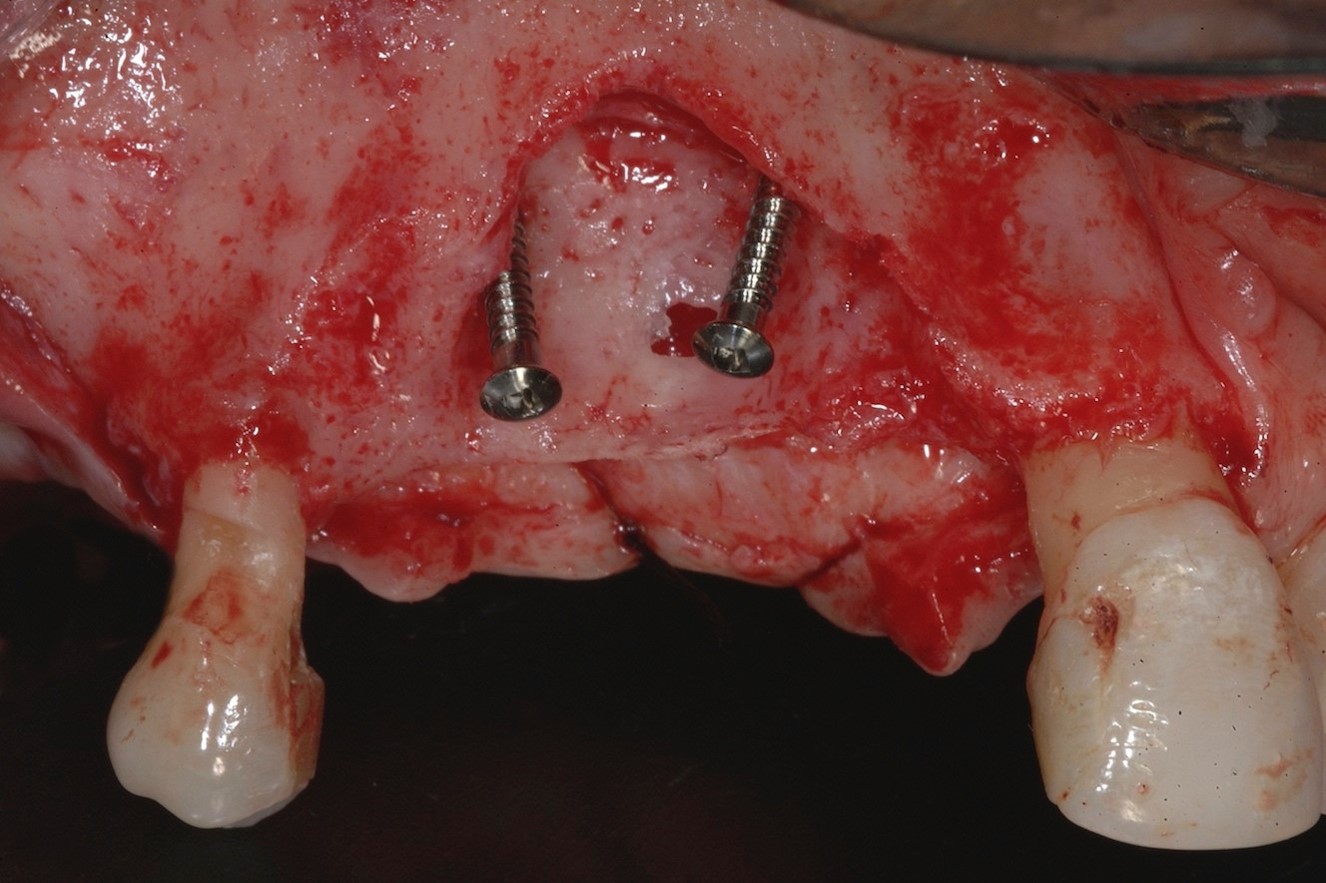

Fig 4. Two dentine screws were placed to support the nonresorbable titanium-reinforced membrane both horizontally and vertically.

Figure 4

Two dentine screws were placed to support the nonresorbable titanium-reinforced membrane both horizontally and vertically and to avoid collapse of the membrane itself toward the defect (Figure 4). A dense e-PTFE membrane was cut and folded to adapt it to the anatomical situation, and the graft was placed (Figure 5). The graft was a mixture of 30% deproteinized bone and 70% autogenous bone chips harvested from the mandibular retromolar area. The membrane was then adapted and fixed with free tacks in the buccal and palatal positions (Figure 6).